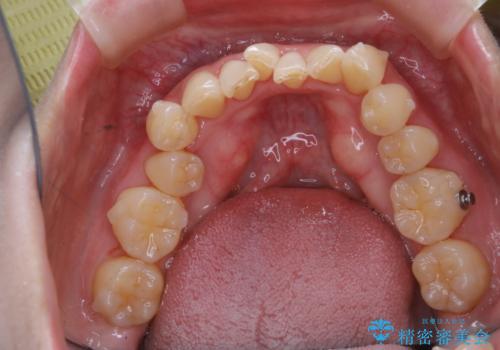

- インビザラインでのマウスピース矯正中に、歯の黄ばみが気になるため綺麗に白くしたいとのことでした。PMTC60分コースを行いました。

PMTC(保険外治療)は、毎日の歯磨きで落としきれない汚れや、コーヒ、紅茶・タバコのヤニなどの着色も除去します。目には見えない歯と歯の間・歯肉の境目・インビザライン中はアタッチメント周囲などに残っているプラーク(歯垢)もしっかり取り除きます。PMTCでは専門的な機械や材料を使用して、徹底的に汚れを除去するため、虫歯・歯周病・口臭予防などにつながります。

またPMTCを行うことで、ご自身本来の歯の色になり自然な明るさになります。